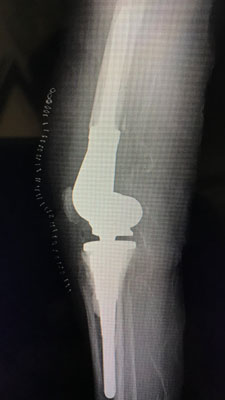

Revision Total Knee Replacement Surgery

Revision Total Knee Replacement means replacement of a joint which has already been replaced once before. There could be various causes for revision of the Primary Total Knee Replacement, but the most common cause is wear and tear of the earlier implant and excruciating knee joint pain.

Revision Total Knee Replacement can be done by conventional method which has been performed for the last 20 years or by newer techniques like computer navigated surgery which has been there since last 5 yrs.